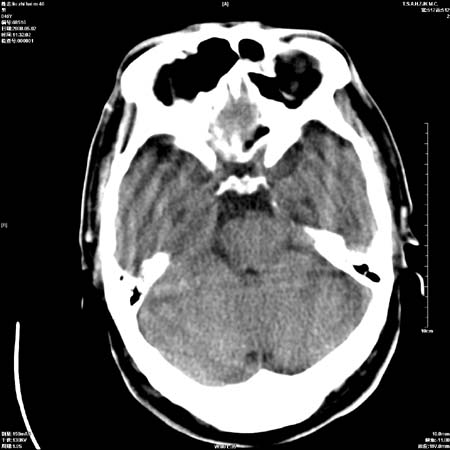

男性   46岁   头晕头痛一周    无任何外伤史    有高血压病史

亚急性硬膜下血肿

考虑双侧慢性硬膜下出血

支持双侧慢性硬膜下血肿。

应该是亚急性(3天——3周)硬膜下出血

亚急性硬膜下血肿;典型。